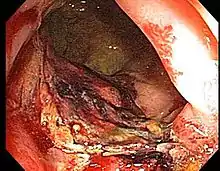

Proctitis is an inflammation of the anus and the lining of the rectum, affecting only the last 6 inches of the rectum.

Doctors can diagnose proctitis by looking inside the rectum with a proctoscope or a sigmoidoscope. A biopsy is taken, in which the doctor scrapes a tiny piece of tissue from the rectum, and this tissue is then examined by microscopy. The physician may also take a stool sample to test for infections or bacteria. If the physician suspects that the patient has Crohn's disease or ulcerative colitis, colonoscopy or barium enema X-rays are used to examine areas of the intestine.